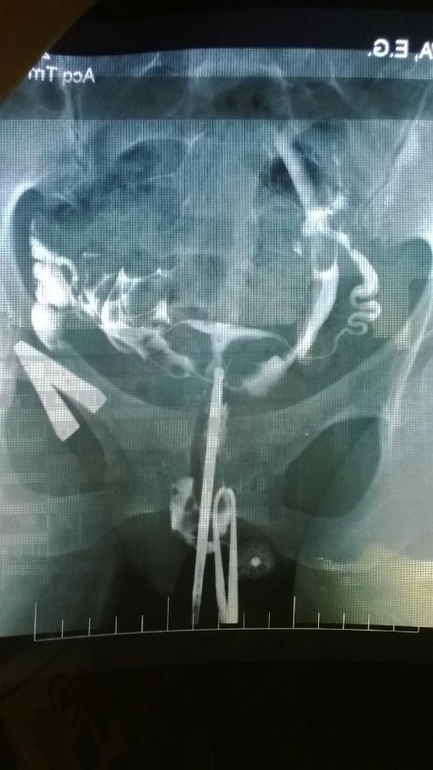

Посмотрите мой снимок ГСГ , плиизз!

Делала ГСГ, врач у меня суровый и не многословный, сделав сказал только что трубы частично проходимы, и не удивительно что вы не беременеете, будем продувать их лекарством. На этом разъяснения закончились.

Выкладываю фото ГСГ и прошу поделиться мнением, кто то что думает? Стоит ли пробовать лекарством или я только потеряю время? И вообще проходимы ли трубы, я в этом снимке ничего не понимаю(((((

справа у вас труба непроходима, я бы не заморачивалась с продуванием , шла бы сразу на лапаро, после нее однозначно будет беременность